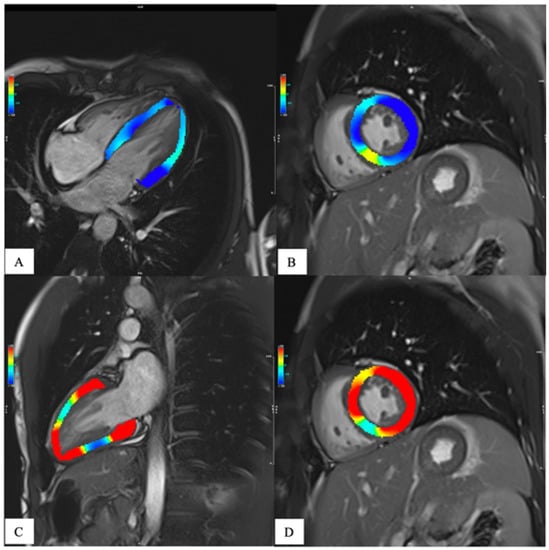

1.2. Magnetic Resonance

- Messroghli, D.R.; Moon, J.C.; Ferreira, V.M.; Grosse-Wortmann, L.; He, T.; Kellman, P.; Mascherbauer, J.; Nezafat, R.; Salerno, M.; Schelbert, E.B.; et al. Clinical recommendations for cardiovascular magnetic resonance mapping of T1, T2, T2* and extracellular volume: A consensus statement by the Society for Cardiovascular Magnetic Resonance (SCMR) endorsed by the European Association for Cardiovascular Imaging (EACVI). J. Cardiovasc. Magn. Reson. 2017, 19, 75. [Google Scholar] [CrossRef]

- Meloni, A.; Gargani, L.; Bruni, C.; Cavallaro, C.; Gobbo, M.; D’Agostino, A.; D’Angelo, G.; Martini, N.; Grigioni, F.; Sinagra, G.; et al. Additional value of T1 and T2 mapping techniques for early detection of myocardial involvement in scleroderma. Int. J. Cardiol. 2023, 376, 139–146. [Google Scholar] [CrossRef]

- Meloni, A.; Pistoia, L.; Positano, V.; Martini, N.; Borrello, R.L.; Sbragi, S.; Spasiano, A.; Casini, T.; Bitti, P.P.; Putti, M.C.; et al. Myocardial tissue characterization by segmental T2 mapping in thalassaemia major: Detecting inflammation beyond iron. Eur. Heart J.-Cardiovasc. Imaging 2023. [Google Scholar] [CrossRef]

- Meloni, A.; Martini, N.; Positano, V.; D’Angelo, G.; Barison, A.; Todiere, G.; Grigoratos, C.; Barra, V.; Pistoia, L.; Gargani, L.; et al. Myocardial T1 Values at 1.5 T: Normal Values for General Electric Scanners and Sex-Related Differences. J. Magn. Reson. Imaging 2021, 54, 1486–1500. [Google Scholar] [CrossRef]

- Meloni, A.; Nicola, M.; Positano, V.; D’Angelo, G.; Barison, A.; Todiere, G.; Grigoratos, C.; Keilberg, P.; Pistoia, L.; Gargani, L.; et al. Myocardial T2 values at 1.5 T by a segmental approach with healthy aging and gender. Eur. Radiol. 2022, 32, 2962–2975. [Google Scholar] [CrossRef]